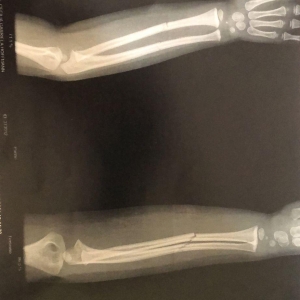

O resultado do exame (imagem acima) apresentou duas fraturas fechadas no braço da criança, que voltou para o hospital Bom Pastor após fazer o Raio-X, e ficou aguardando em um leito a transferência para algum hospital da região a fim de receber atendimento especializado.

A reportagem do Portal está acompanhando o caso da criança de 3 anos, moradora de Nova Santa Rosa, que teve duas fraturas fechadas no braço direito após cair enquanto brincava em uma cama elástica na manhã de quinta-feira (19).

A criança foi levada ao Hospital Bom Pastor no início da tarde de ontem e, por volta das 16h00, foi encaminhada à Palotina para fazer Raio-X no Hospital da Unimed, onde o município tem convênio por não estar realizando o exame - a sala está há tempo fechada e até hoje não foi colocada em funcionamento pela prefeitura.